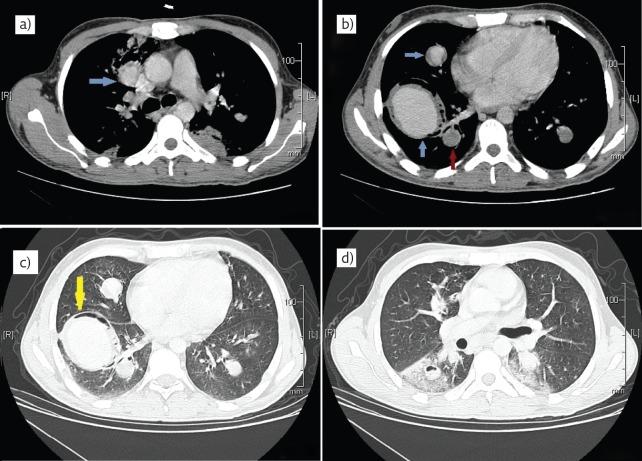

Case report: A rare cause of haemoptysis in a male with unprovoked deep venous thrombosis.

A case report depicting a rare cause for the unusual entity of pulmonary artery aneurysm http://ow.ly/YvA1y.